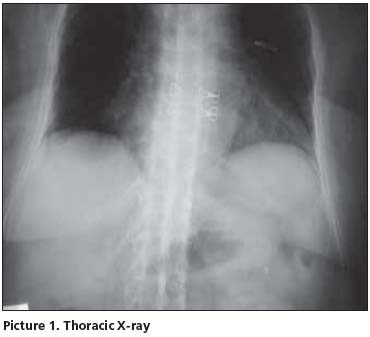

Her postero-anterior chest x-ray was evaluated as normal. In thoracic (Picture 1) and lumbosacral (Picture 2) graphs, marked squaring in her vertebras, shiny corners, symmetric syndesmophytes, bamboo spine, trolley track sign, osteoporosis and left faced scoliosis were observed. In pelvic x-ray her sacroiliac joints were normal. There were enthesopathic changes in the localization of the insertion of achilles tendon in calcaneus posterior bilaterally (picture 3). In magnetic resonance imaging (MRI) and conventional radiography, bilateral sacroiliac joints were regular and joints cartilage were normal (Picture 4,5). There were not any pathological signal changes in the bone surfaces that form the joints and the soft structures that were examined. Depending on the current clinical status and the radiography and imaging tests, the patient was defined as spondyloarthropathy (SpA).

Diagnosing axial SpA [Ankylosing Spondylitis (AS) and undifferentiated SpA(uSpA) with predominant axial involvement but without radiographic sacroiliitis] in the absence of radiographic sacroiliitis poses a major challenge to many physicians. In the absence of diagnostic criteria, classification criteria are often used to aid the diagnostic process in daily practice. The most often cited classification criteria for SpA are the Europian Spondylarthropathies Study Group (ESSG) criteria that were proposed in 1991. According to these criteria, in the absence of sacroiliitis; patients with inflammatory spinal pain or synovitis (asymmetric, predominantly in the lower limbs) in addition to any one of the following (positive family history, psoriasis, inflamatory bowel disease, alternate bottock pain, enthesopathy) are classified as seronegative SpA with 77% sensitivity and 89% specificity. In the presence of sacroiliitis, sensitivity is 86% and specificity is 87%[1]. However in a recent study from Spain, it was observed that the performance of the ESSG criteria as diagnostic criteria in daily practice was moderate: only 46.6% of patients with possible SpA who met the ESSG criteria at entry into the study were judged by their rheumatologist to have SpA after 5 years of follow up[2]. The typical radiographic changes of AS are seen primarily in the axial skeleton, especially in the sacroiliac, discovertebral, apophyseal, costovertebral, and costotransvers joints[3]. Syndesmophyits seen in AS and entheropathic arthiritis are usually symmetrical and bilateral, while that are seen in reactive arthiritis and psoriatic arthritis are nonmarginal, rough and asymmetrically located[4]. The radiological appearance of arthritic changes in sacroiliac joints has been regarded as a hallmark of AS according to Modified New York Criteria[5]. In AS patients in addition to sacroiliitis, arthritic changes in the spine visualized by x-ray develop in 57- 88% of the patients[6,7]. In literature, there were AS patients with typical clinical features but no radiological sacroiliitis[8]. Khan et al reported that radiographic sacroiliitis is frequent in AS but is not an early or obligate manifestation of the disease. In particular, relatives of AS with IBP may not show radiographic sacroiliitis even after long follow-up[9]. Rudwaleit reported that in a small proportion of AS patients may never develop radiolographic sacroiliitis despite having IBP for many years. SpA patients with predominantly axial symptoms should be considered as having a same disease entity as AS patients, independent from the presence of radiographic sacroiliitis[10]. In one study 60% of SpA patients had developed definite AS after 10 years of follow-up. It took an average of 9 years (+/-6 years) for radiological sacroiliitis to appear in these patients. A further 20% still had chronic uSpA and might have developed radiological sacroiliitis if their follow-up had been continued for a longer time[11]. Again in another family study, radiographic evidence of sacroiliitis was found in 40% of patients with a symptom duration of <10 years, 70% with symptoms for 10-19 years, and 86% with symptoms for ≥ 20 years[12]. The morphological changes used to assess spinal involvement in x-ray were syndesmophytes, shining corners, squaring, arthritis of the apophyseal joints, spondylodiscitis, bamboo spine and trolley track sign[13]. Descriptions of spinal x-ray changes typical of AS without concomitant radiological sacroiliitis are thus relatively uncommon. Besides, Moll reported that these spinal x-ray changes develop later in the course of AS and usually after radiological sacroiliitis is evident.[14]. MRI is considered to be very helpful in detecting signs of sacroiliitis that are not yet visible in x-ray[15]. Although our HLA B27 positive patient has been suffering from IBP for 10 years, no sacroiliitis was detected in her pelvic x-ray and MRI. However in her throracic and lomber x-ray, all radiological abnormalities such as squaring, shiny corner, syndesmophytes, bamboo spine, trolley track sign were clearly present. In her foot x-ray, bilateral calcaneal enthesopathy was detected.